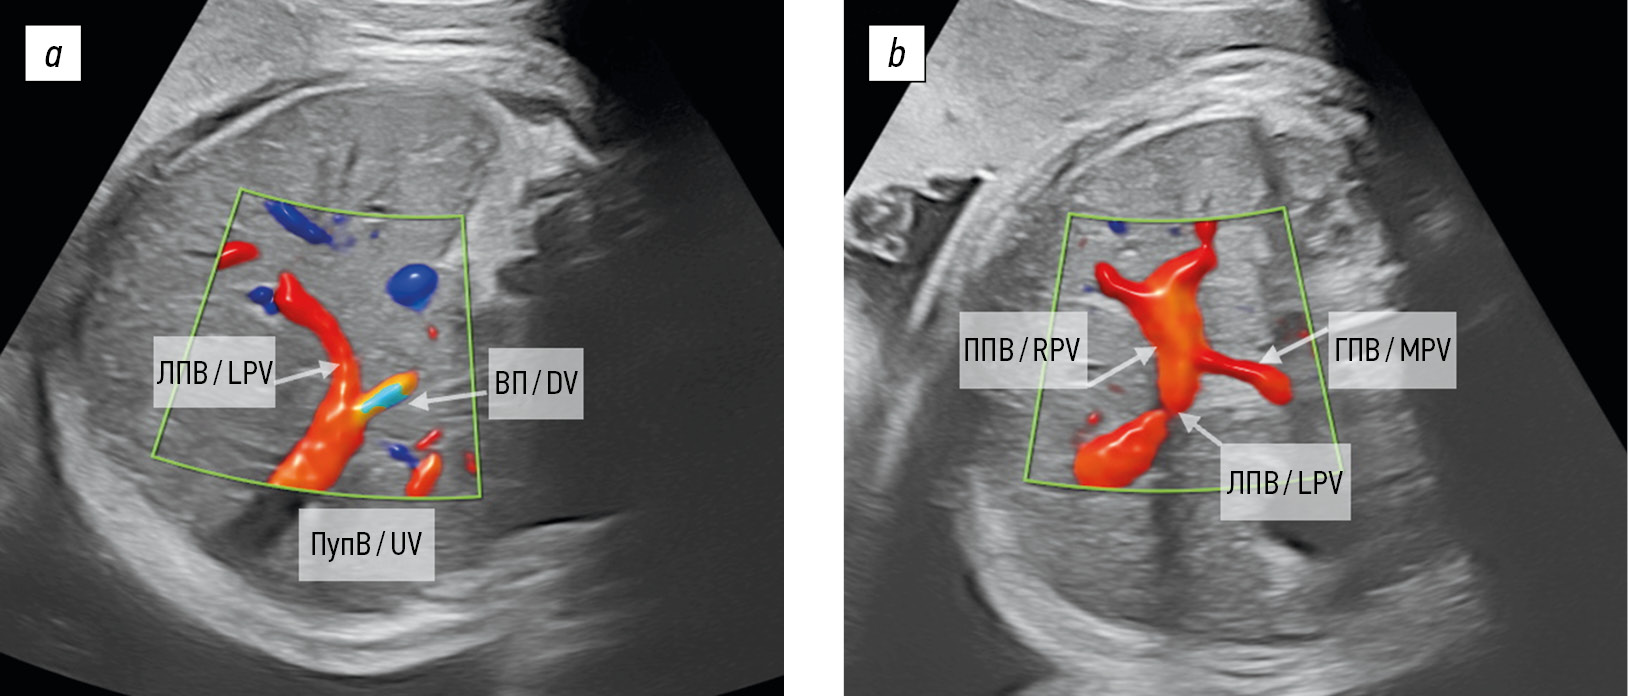

Рис. 1. Схема строения умбиликально-портальной венозной системы плода: а — поперечный срез брюшной полости плода, стрелками показаны физиологические направления кровотока в печени плода (адаптировано из [19]); b — визуализация умбиликально-портальной венозной системы плода в режиме 3D HD-Flow. ПупВ — пупочная вена; ЛПВ — левая портальная вена; ППВ — правая портальная вена; ГПВ — главная портальная вена; НПВ — нижняя полая вена; ВП — венозный проток

Fig. 1. The schematic view of the fetal umbilical-portal venous system: a, cross section of the abdominal cavity of the fetus, arrows indicate physiological directions of blood flow in the fetal liver (adapted from [19]); b, visualization of the fetal umbilical-portal venous system in 3D HD-Flow mode. UV, umbilical vein; LPV, left portal vein; RPV, right portal vein; MPV, main portal vein; НПВ, inferior vena cava; DV, ductus venosus